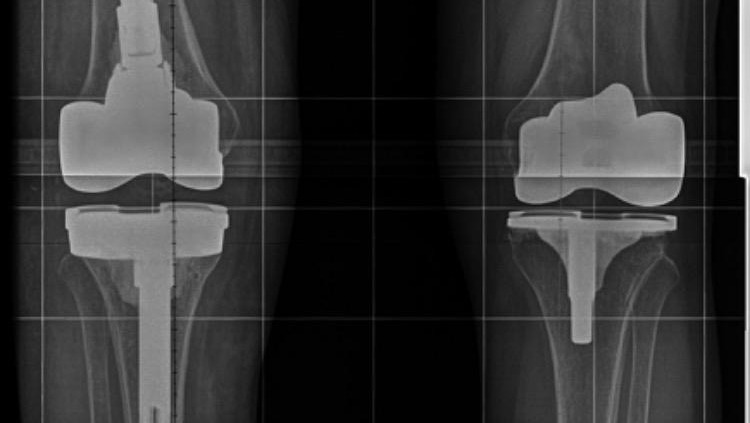

- A double knee replacement surgery (2018)

- Surgery to install a temporary knee, which kept me bedridden for 6 months

- State-of-the-art organic material to rebuild & reinforce the portions of my femur and tibia bones that were consumed by staph infection

- SUCCESSFUL permanent knee surgery 2022

- Una doble cirugía de reemplazo de rodilla (2018)

- Cirugía para instalar una rodilla temporal, lo que me mantuvo postrado en cama durante 6 meses.

- Material orgánico de última generación para reconstruir y reforzar las partes de los huesos de mi fémur y tibia que fueron consumidos por una infección por estafilococos

- CIRUGÍA DE RODILLA PERMANENTE EXITOSA 2022